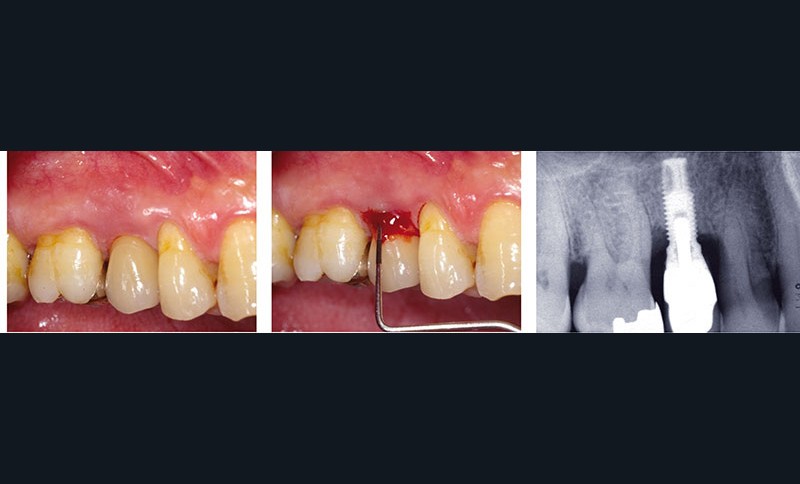

Les péri-implantites sont des maladies inflammatoires d’origine infectieuse qui se manifestent cliniquement par une inflammation des tissus mous, avec un saignement au sondage et/ou parfois une suppuration, ainsi qu’une perte d’attache et une profondeur de poche au sondage supérieure à 5 mm. Radiographiquement, cet état se manifeste par l’existence d’une perte osseuse, correspondant à une exposition de plusieurs spires de l’implant (fig. 1).